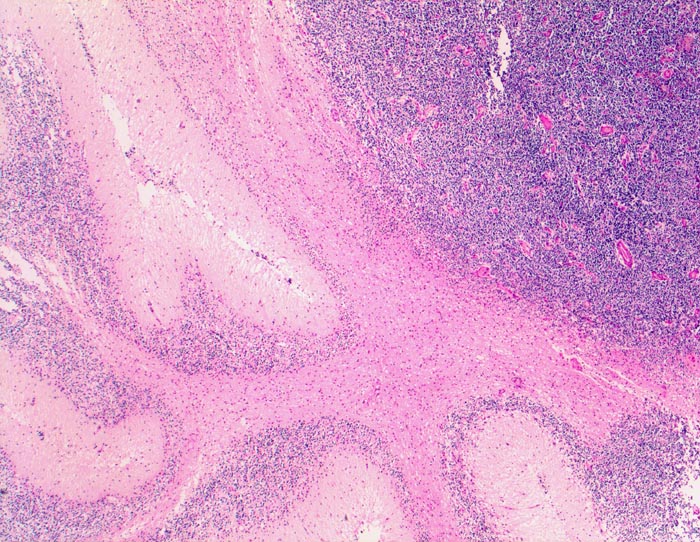

PathoPic – image database / PathoPic ID 5241 - Medulloblastom

Medulloblastom

maligner Tumor

Kleinhirn

Nervensystem

Beschreibung

Klinik

Knabe mit Kopfschmerzen und morgendlichem Erbrechen ohne Übelkeit

Bilder Typ

Histologie

Vergrösserung

25

Alter

7

männlich